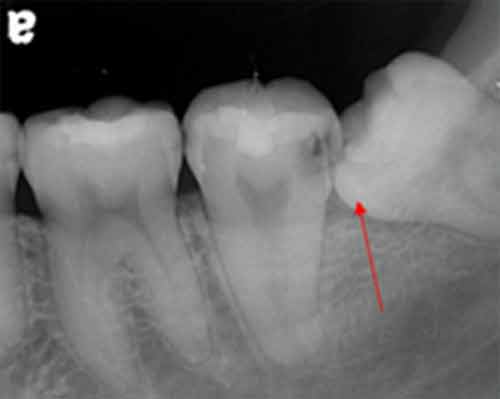

智齒造成蛀牙

2008年4月拍攝